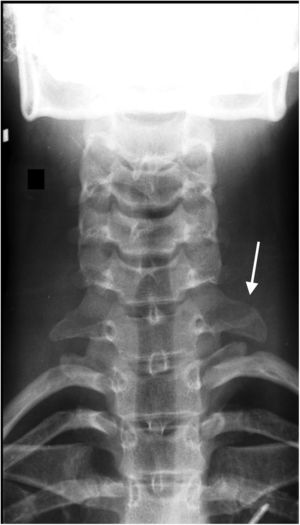

We conducted basic and needle-EMG examinations and found a severe inferior brachial plexopathy associated with severe chronic neurogenic impairment in the C8 and T1 innervated muscles. Further examination with magnetic resonance imaging (MRI) excluded any discoradicular conflict at the level of C8 and T1 but identified small excess of fat and edema in the form of a “teardrop” surrounding C8 and T1 suggesting compression of these nerves at the thoracic outlet level (Fig. 2). A standard radiography of the cervical spine clearly showed an abnormally elongated left C7 transverse process (Fig. 3). A diagnosis of TN-TOS was concluded.